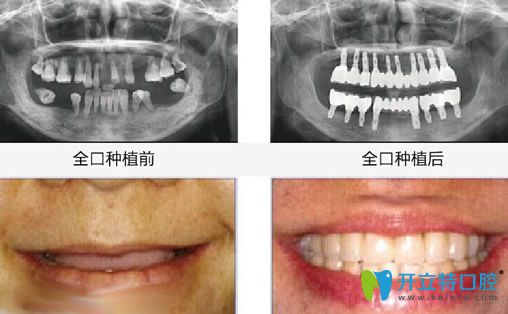

昆明竹子口腔怎么樣?國醫(yī)生All-on-4即刻種植牙案例效果來見證:

種植前:牙齒幾乎掉完,只剩下殘牙根;

種植后:無論是咀嚼力度,還是外觀都和真牙一樣。